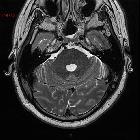

MRI

A stalk-like connection to the clivus is usually seen if high-resolution images are obtained.

Apart from the characteristic location (retroclival, prepontine, and intradural), MRI findings are non-specific, with signal similar to CSF:

- T1: hypointense

- T2: hyperintense

- T1 C+ (Gd): variable, however, most cases have not shown substantial enhancement